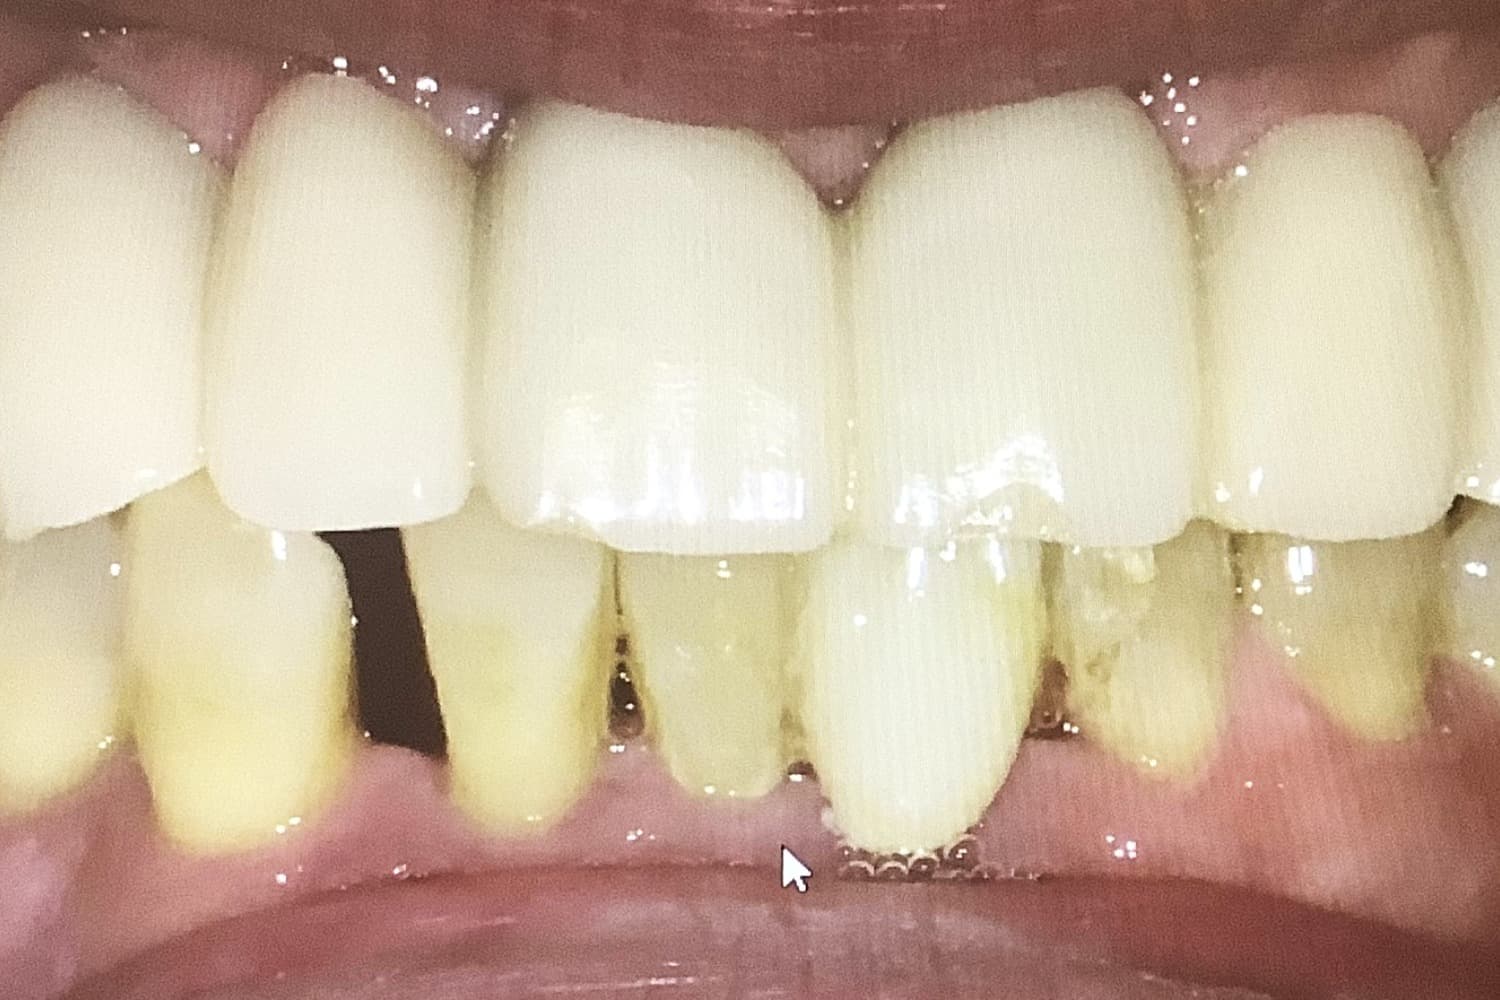

上顎のインプラント治療

After

上顎に8本インプラントを埋入手術しブリッジ冠を用いて修復した

年齢

50

性別

男性

主訴

上顎の総入れ歯が嫌なのでインプラントにしたい

治療期間

8ヵ月

治療回数

8回

費用

2,860,000円

副作用・リスク

・全身疾患の有無や骨の状態によってインプラント体が骨と生着しない可能性がある ・術後患部が腫れたり痛みが生じたりする可能性がある